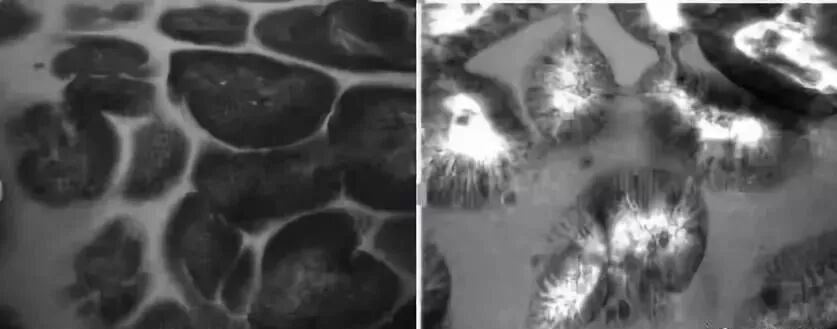

萎缩性胃炎大多依靠内镜进行诊断,在内镜下可能会呈现花斑样改变。在共聚焦激光显微内镜下可以清晰地看到胃内腺体的萎缩,可伴有肠上皮化生,表现为胃内粘膜被肠道绒毛样上皮所取代,并可能有大而黑的杯状细胞

上图:共聚焦激光纤维内镜下可见上皮呈柱状排列,胃小凹数目明显减少,小凹开口扩大(无明显肠化);图2:共聚焦激光显微内镜下可见胃小凹呈绒毛状,可见较多杯状细胞,腺体分散稀疏,间隔增宽(肠化明显)。